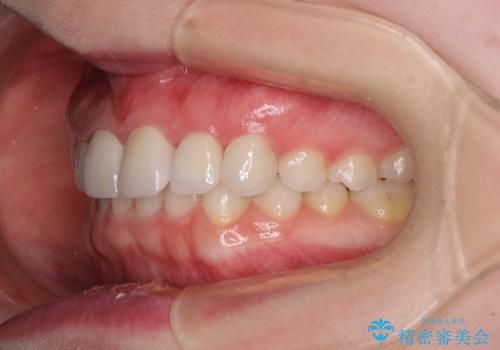

- 前歯の歯並びと虫歯を気にして来院された患者様です。

上下前歯の歯列不正はインビザラインにより歯列を整え、その後に、前歯5本をオールセラミッククラウンにて補綴治療することとしました。

矯正治療前に前歯のむし歯治療を行ったものの、樹脂で充填するには虫歯が広範囲であったため、審美的に問題がありました。

矯正治療にて歯並びを整えた後に、虫歯の大きかった5本の歯をセラミッククラウンにて補綴し、明るい口元になりました。